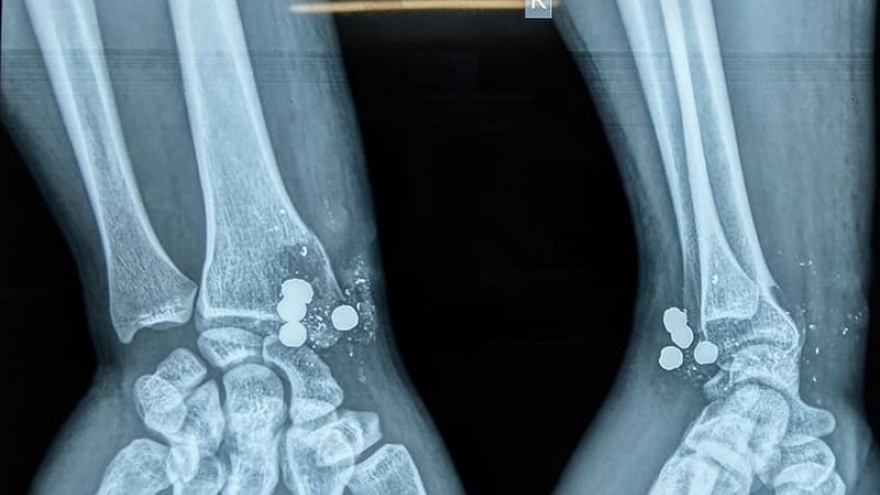

Súng kíp phát nổ bắn 5 viên đạn vào cổ tay người đàn ông

VOV.VN -Thấy nhà bạn có khẩu súng kíp, anh Th lấy xuống xem thì bất ngờ súng phát nổ, 5 viên đạn cắm thẳng vào cổ tay người này.